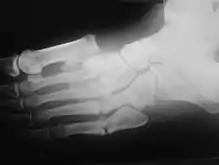

Radiologic findings

First, it is important to recognize that two types of abnormality may be detected. One is termed atrophic, in which there is osteolysis of the distal metatarsals in the forefoot. The more common form of destruction is hypertrophic joint disease, characterized by acute peri-articular fracture and joint dislocation. According to Yochum and Rowe, the "6 D's" of hypertrophy are:

The natural history of the joint destruction process has a classification scheme of its own, offered by Eichenholtz decades ago:

Stage 0: Clinically, there is joint edema, but radiographs are negative. Note that a bone scan may be positive before a radiograph is, making it a sensitive but not very specific modality.

Stage 1: Osseous fragmentation with joint dislocation seen on radiograph ("acute Charcot").

Stage 2: Decreased local edema, with coalescence of fragments and absorption of fine bone debris.

Stage 3: No local edema, with consolidation and remodeling (albeit deformed) of fracture fragments. The foot is now stable.

Atrophic features:

- "Licked candy stick" appearance, commonly seen at the distal aspect of the metatarsals

- Diabetic osteolysis

- Bone resorption